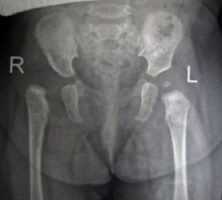

Рентгенограммы больной Т., 10 месяцев. Диагноз: врожденный вывих бедра справа.

2. Открытое вправление бедра в сочетании с транспозицией вертлужной впадины (подвздошной остеотомией таза)

Применяется у детей старше 1 года в тех ситуациях, когда врожденный вывих бедра сочетается с выраженным недоразвитием вертлужной впадины.